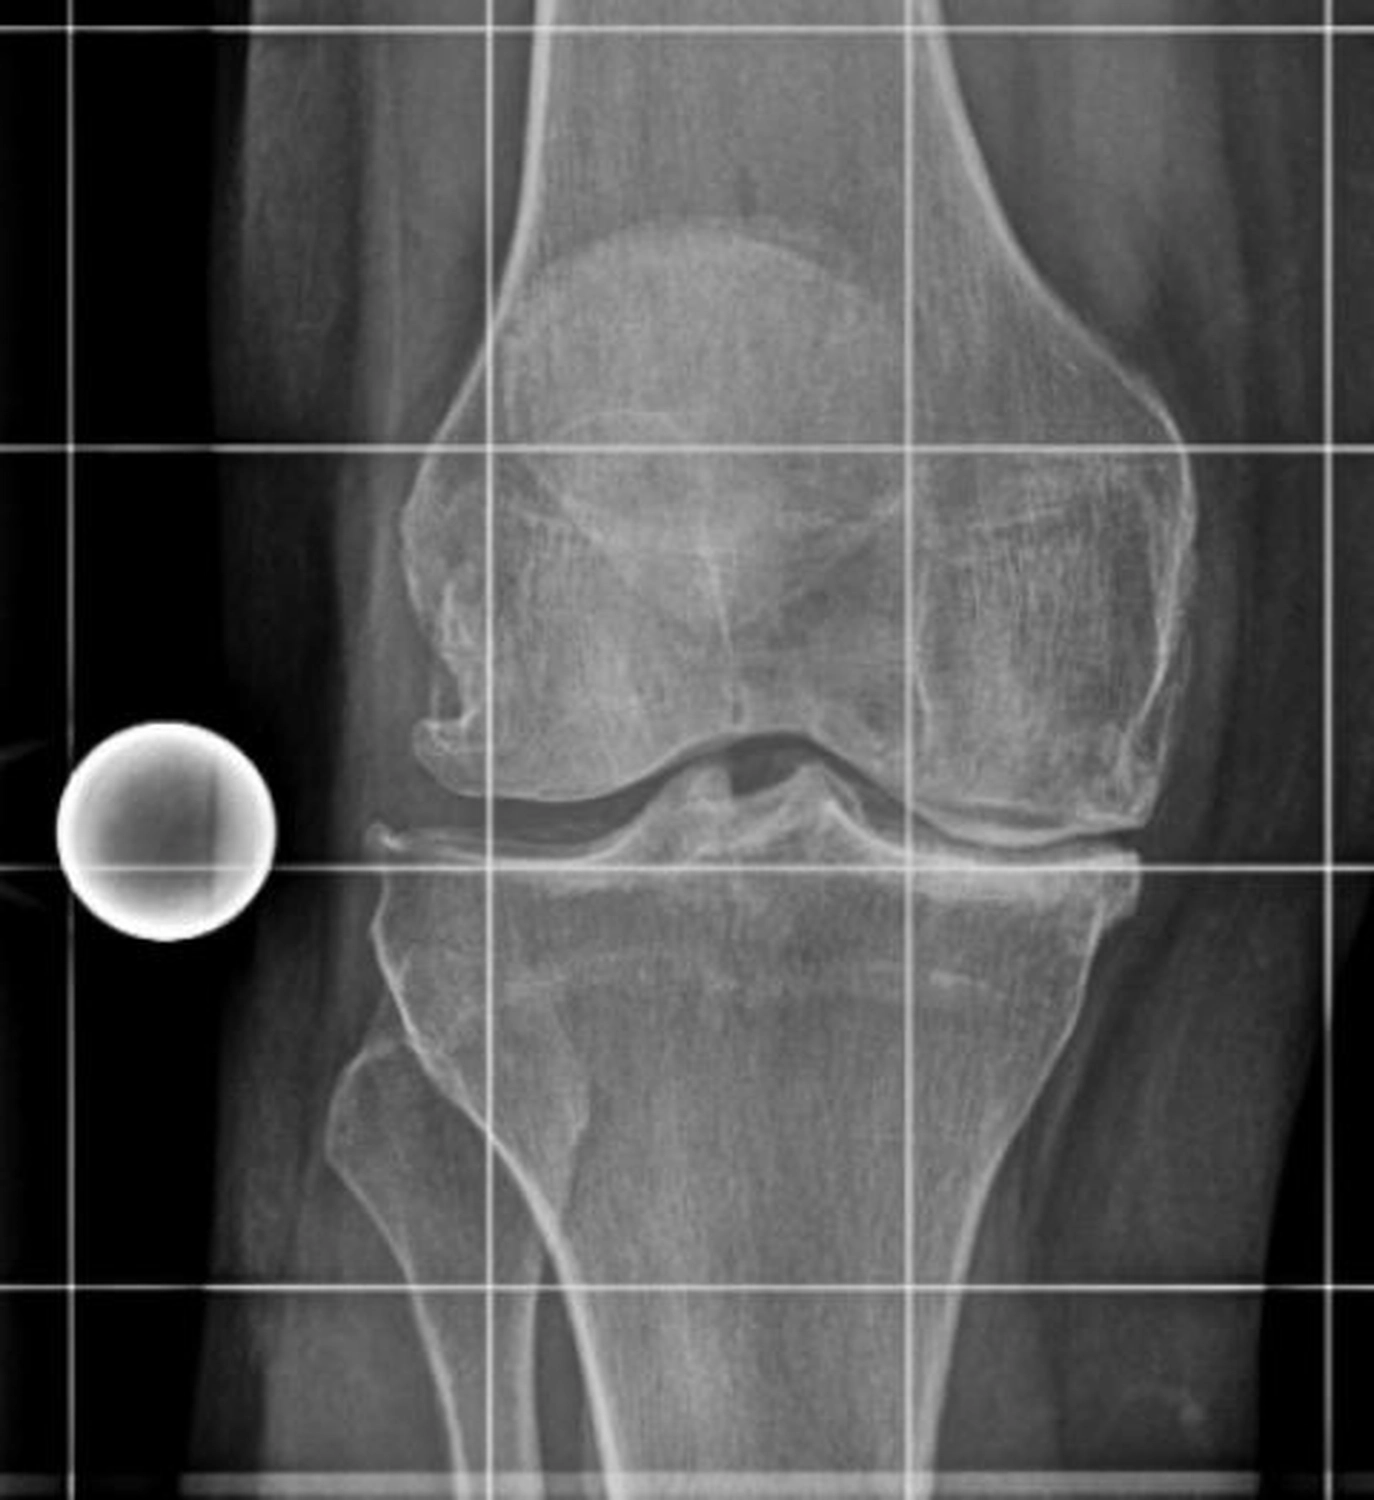

Das Kniegelenk ist das größte und eines der am stärksten belasteten Gelenke des menschlichen Körpers. Bei jeder Bewegung – Gehen, Treppensteigen, Hocken oder Stehen – wirken erhebliche Kräfte auf die Gelenkflächen von Oberschenkelknochen (Femur), Schienbein (Tibia) und Kniescheibe (Patella).

Diese Flächen sind von einer glatten Knorpelschicht überzogen, die wie ein Stoßdämpfer wirkt und ein reibungsloses Gleiten ermöglicht. Im Verlauf des Lebens kann sich dieser Knorpel jedoch abnutzen oder geschädigt werden – man spricht dann von einer Arthrose.

Die Kniegelenksarthrose (Gonarthrose) kann viele Ursachen haben. Häufig sind mehrere Faktoren beteiligt, die sich gegenseitig verstärken.

Eine Knie-Totalendoprothese (Knie-TEP) wird empfohlen, wenn:

Die Entscheidung wird stets individuell gemeinsam zwischen Patienten und Arzt getroffen.